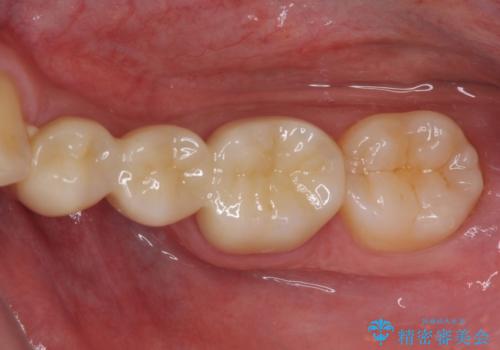

外れてしまった銀歯の詰め物 オールセラミックブリッジにて審美補綴